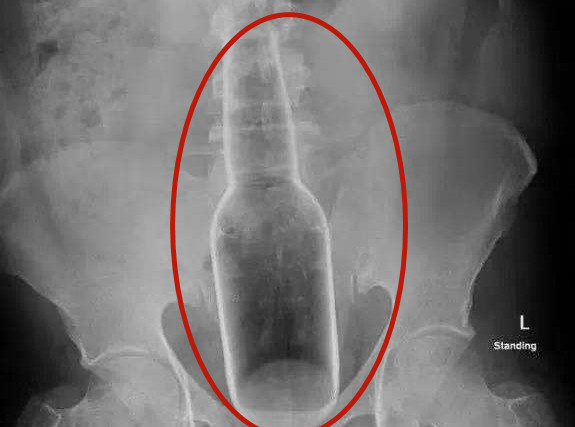

一個玻璃瓶從肛門,硬生生的塞進直腸,直接頂在下腹中部,這張X光片瞬間讓醫生全傻

眼了。廣東省東莞市中西醫結合醫院肛腸科日前就接診了這樣一例特殊病例,醫護人員從

一名男子的直腸內取出了一個18公分長的超大玻璃瓶。

據《南都都市報》報導,「患者的腹部可明顯摸到堅硬異物,在直腸距肛門約5公分處就

可觸及異物底部。」東莞市中西醫結合醫院主任醫師林軍表示,當時接診患者後,經過了

診查,便建議急診手術將異物取出。

在徵得患者同意後,醫生為患者行「直腸異物取出術」。整個手術過程順利,最終,醫護

人員將一個長約18公分、直徑5公分的超大玻璃瓶從患者直腸中成功取出。